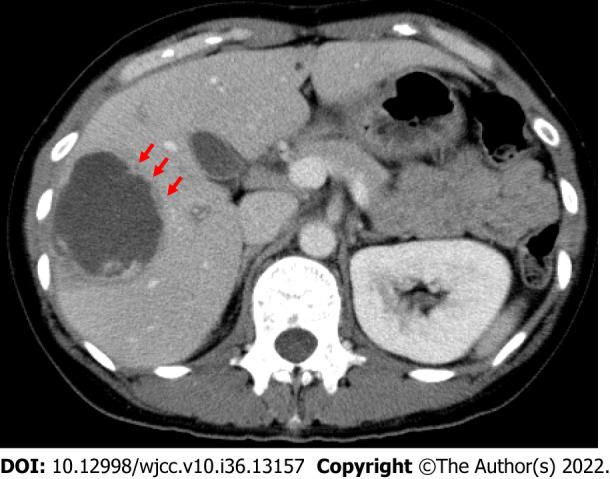

Amebic liver abscesses (ALAs) are the most commonly encountered extraintestinal manifestation of human invasive amebiasis, which results from () spreading extraintestinally. Amebiasis can be complicated by liver abscess in 9% of cases, and ALAs led to almost 50000 fatalities worldwide in 2010. Although there have been fewer and fewer cases in the past several years, ALAs remain an important public health problem in endemic areas. causes both amebic colitis and liver abscess by breaching the host's innate defenses and invading the intestinal mucosa. Trophozoites often enter the circulatory system, where they are filtered in the liver and produce abscesses, and develop into severe invasive diseases such as ALAs. The clinical presentation can appear to be colitis, including upper-right abdominal pain accompanied by a fever in ALA cases. Proper diagnosis requires nonspecific liver imaging as well as detecting anti- antibodies; however, these antibodies cannot be used to distinguish between a previous infection and an acute infection. Therefore, diagnostics primarily aim to use PCR or enzyme-linked immunosorbent assay to detect . ALAs can be treated medically, and percutaneous catheter drainage is only necessary in approximately 15% of cases. The indicated treatment is to administer an amebicidal drug (such as tinidazole or metronidazole) and paromomycin or other luminal cysticidal agent for clinical disease. Prognosis is good with almost universal recovery. Establishing which diagnostic methods are most efficacious will necessitate further analysis of similar clinical cases.